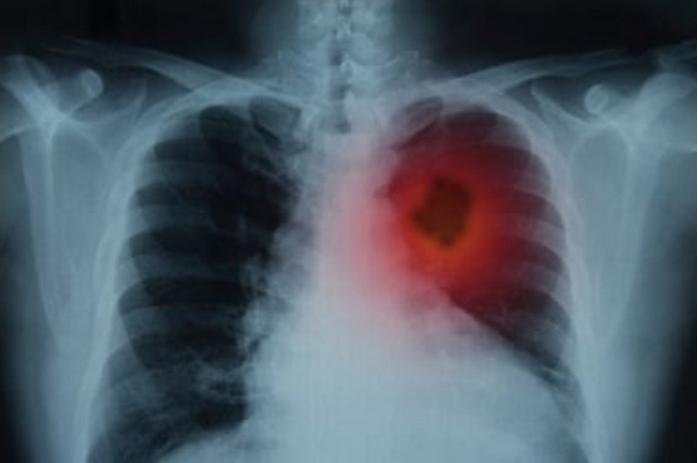

88 Persen Pasien Kanker Paru, Wafat di Tahun yang Sama saat Kanker Ditemukan

kanker paru merupakan penyebab kematian tertinggi pada pasien kanker, karena biasanya pasien datang terlambat ...